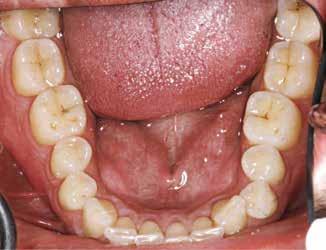

BAGGRUND – Denne kasuistik beskriver en patient, hvor der blev valgt protetisk behandling i ung alder.

PATIENTTILFÆLDE – En niårig pige havde stort behandlingsbehov og smerter fra tænderne på grund af tandudviklingsforstyrrelse. Der var flere gange forsøgt restaurering med komposit, som ikke fungerede. Laminater i feldspatkeram blev valgt for at fjerne mindst mulig tandsubstans, øge holdbarheden på restaureringerne og forbedre æstetikken. Patientens motivation, meninger og kooperationsevne var vigtige for behandlingsvalget, da behandlingen var tidkrævende og til tider udmattende for en ung patient.

KONKLUSION – Resultatet var vellykket og medførte forbedret livskvalitet. Protetisk behandling med adhæsiv teknik kan være et godt behandlingsalternativ for børn og unge på ret indikation.

EMNEORD Adhesives | amelogenesis imperfecta | ceramics | pediatric dentistry | quality of life

Protetisk behandling med adhæsiv teknik –et alternativ i ung alder?

Accepteret til publikation den 26. marts 2024 Tandlægebladet 2024;128:758-62

VED BEHOV FOR OMFATTENDE TANDRESTAURERING HOS BØRN OG UNGE kan flere behandlingsalternativer være aktuelle (1). Restaurering med fyldningsmaterialer er som regel førstevalg, men i nogle tilfælde fungerer dette ikke godt nok. Ved udarbejdelse af behandlingsplan må klinikerne kende til mulige behandlingsalternativer og vurdere disse på baggrund af kliniske fund, patientens symptomer og kooperationsevne samt patientens ønsker og planlægge behandling i et livsløbsperspektiv.

PATIENTTILFÆLDE

Beskrivelse af patienten Patienten blev henvist til specialistuddannelsen i pædodonti ved Universitetet i Oslo, da hun var syv år gammel, for diagnostik og behandling af tandudviklingsforstyrrelse i primære og permanente tandsæt. Pigen havde pollenallergi, var ellers sund og rask og havde intet medicinforbrug.

Klinisk undersøgelse viste emaljehypoplasier og hypomineralisering på 1+, +1, 2-, 1-, -1 og -2 (Fig.1). Hun havde Angle klasse II, pladsmangel i begge kæber og agenesi af -5. Der var isninger ved spisning og tandbørstning. Fundene var forenelige